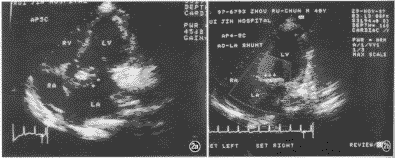

感染性心内膜炎导致主动脉-左房瘘一例

患者男,40岁,既往体健。1个月前开始发热,热型不规则,体温达39~40℃。曾在当地医院接受治疗,间断使用多种抗生素等药物。因病情未见减轻,并出现咳嗽、胸闷、心悸和夜间阵发性呼吸困难1周转来我院。入院时体温38℃,心率96次/分,血压120/75mm Hg(1 mm Hg=0.133 kPa),精神较萎靡,贫血貌,红细胞2.63×1012 /L,血沉120mm/1 h。听诊于胸骨左缘闻及连续性杂音,以收缩期为主,粗糙响亮;主动脉瓣区2~3级喷射性收缩期杂音 ......